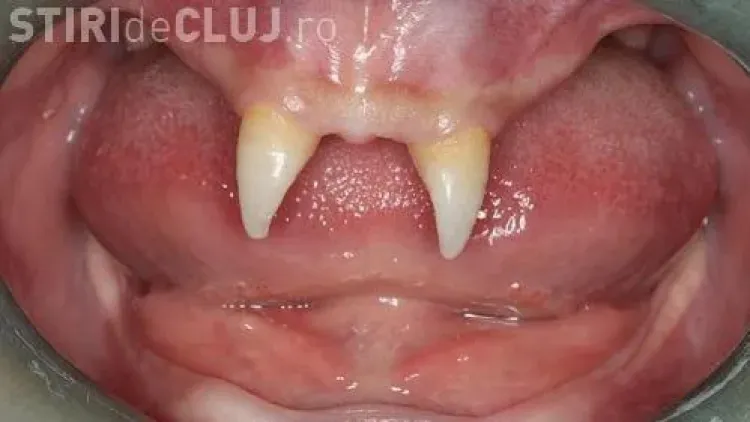

Un băiat din China i-a uimit pe medici, după ce i-au crescut doi canini foarte ascuţiţi, neavând alţi dinţi în gură.

Medicii i-au spus că cei doi canini vor fi operați când va fi un adult și că totul va costa 10.000 de euro. ”Nu are prieteni şi își dă din ce în ce mai mult seama cât de diferit este faţă de ceilalţi copii”, a spus mama copilului, care a adăugat că fiul ei a devenit mai izolat şi agresiv cu colegii, conform rtv.net.